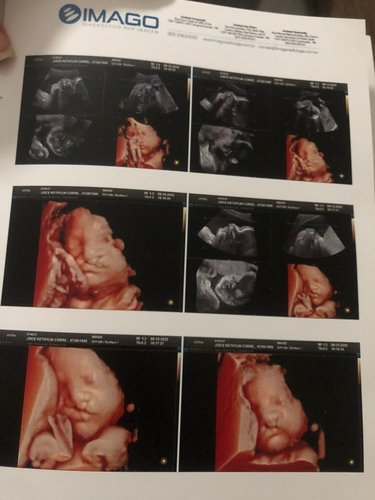

Olá me Chamo Joice sou a mãe do pequeno Lorenzo , que foi diagnosticado com Lábio Leporino e fenda Palatina desde o 5 mês de gestação.

Que no caso do meu filho foi diagnosticado com os dois lados do lábio superior com a fenda junto com o palato aberto também.